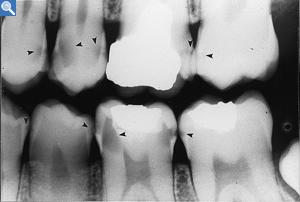

A identificação das lesões de cárie pode ser feita através da visão direta dos dentes, no emprego do fio dental (se este ficar preso entre os dentes pode ser um sinal de lesão de cárie) e de radiografias (sendo esta última realizada apenas pelo dentista).

Carie Interdenteal as vezes só é identificavel após exame radiológico